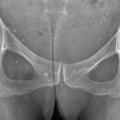

La forme pseudorhumatoïde est rare (5 %), simulant une polyarthrite rhumatoïde (diagnostic différentiel), avec parfois des signes systémiques d’inflammation (élévation de la vitesse de sédimentation et de la CRP). Le diagnostic repose sur la mise en évidence des cristaux de PPC. La radio peut mettre en évidence des calcifications des cartilages articulaires (fig. 6) et des fibrocartilages (fig. 7, 8, 9 et 10). L’échographie (plus sensible) peut mettre en évidence des dépôts de PPC, qui apparaissent comme une fine bande hyperéchogène au sein des cartilages hyalins et comme des points scintillants dans les fibrocartilages ou dans la membrane synoviale. Dans l’arthrite chronique à PPC, lespossibilités thérapeutiques sont, par ordre de préférence : colchicine (de 0,5 à 1 mg/j), petites doses de cortisone, parfois les AINS per os (mais leur prescription est souvent limitée par les comorbidités chez les patients âgés), méthotrexate et l’hydroxychloroquine. Il n’y a pas aujourd’hui de traitement « de fond », mais des molécules sont à l’étude.

L’arthrose associée aux dépôts de PPC touche en particulier les genoux, avec une symptomatologie chronique et/ou des accès aigus cristallins. Par comparaison avec l’arthrose idiopathique, elle serait à l’origine d’une symptomatologie plus inflammatoire, toucherait des articulations inhabituelles (radiocarpienne, carpienne, gléno-humérale, médio-pied et arrière-pied, cheville) et serait associée à plus d’ostéophytes et de géodes. Cette arthropathie dégénérative peut s’accompagner de lésions structurales sévères avec disparition rapide de l’interligne (arthropathies destructrices : hanches, genoux, poignets, coudes). Les objectifs et les modalités thérapeutiques sont identiques à ceux d’une arthrose idiopathique. Aucun traitement ne permet la dissolution des cristaux de PPC.